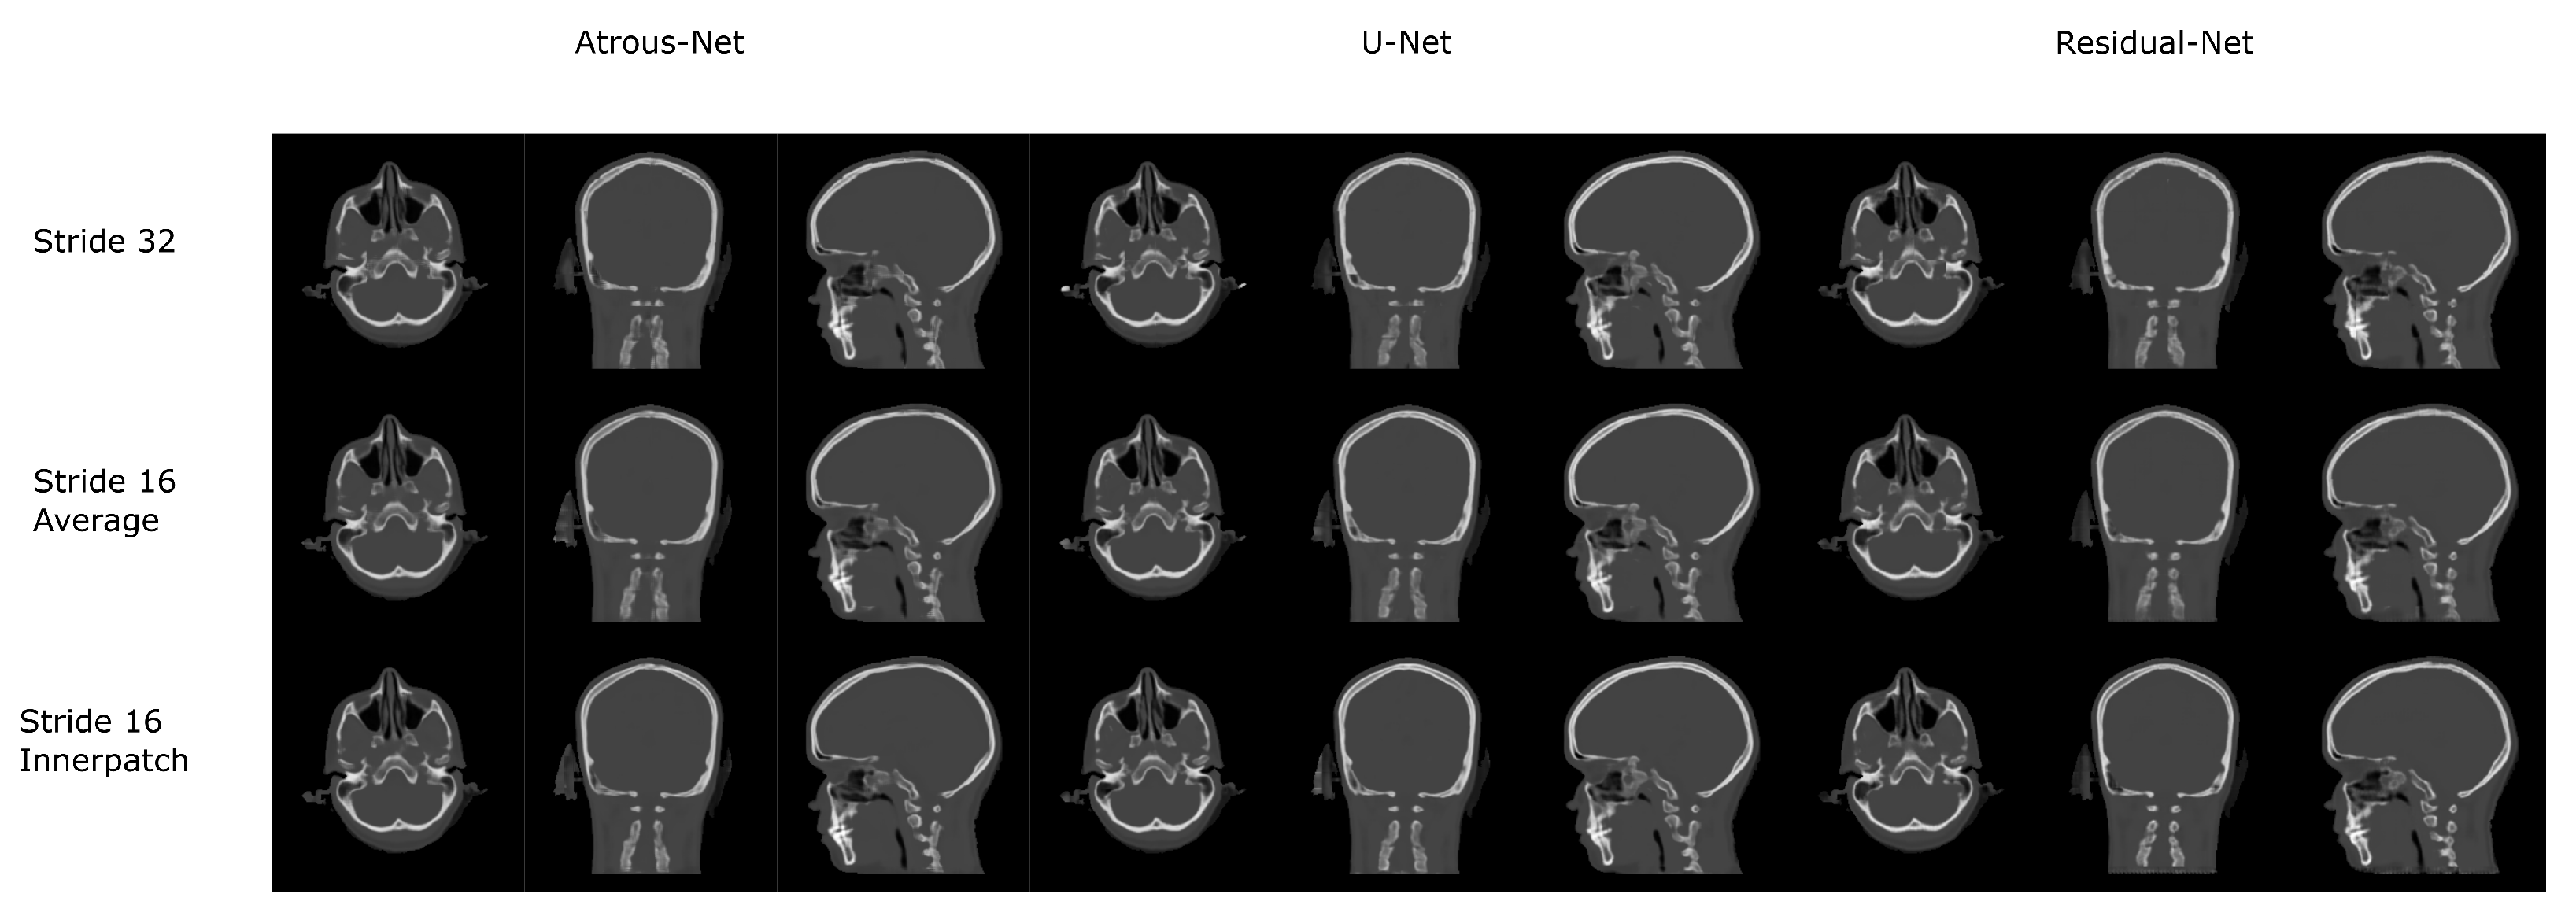

3.1. Head Dataset Results

The results for all tissues using the head dataset are depicted in Table 1, Table 2 and Table 3; the results using only the bone voxels are detailed in Table 4, Table 5 and Table 6; the results using only the fat voxels are detailed in Table 7, Table 8 and Table 9; and the results using only the soft-tissue voxels are detailed in Table 10, Table 11 and Table 12. The best performing 2D network for the head dataset was the Residual-net. The results presented a MAE of 99.83 HU, a PSNR of 24.83 and a Pearson Coefficient of 0.931 in all tissues, and a MAE of 326.33 HU, a PSNR of 19.04 and a Pearson Coefficient of 0.826 in bone voxels. The ANOVA test revealed a statistically significant effect of the 2D architectures for MAE results (all tissues: F 2 , 36 = 91.1 , p < 0.001 ; bone: F 2 , 36 = 74.2 , p < 0.001 ) and PSNR results (all tissues: F 2 , 36 = 99.3, p < 0.001 ; bone: F 2 , 36 = 85.6, p < 0.001 ). A paired t-test was used to compare the Residual-net to the other networks reporting also statistically significant differences in the MAE and in the PSNR (Table 13). Using 2D convolutions, the Atrous-net and the U-net performed 5% and 18% worse than the residual-net, respectively. Moreover, the U-net network was clearly behind the other networks using 2D convolutions. Nevertheless, the U-net in 3D-16 obtained a MAE of 89.54 HU, a PSNR of 25.69 and a Pearson Coefficient of 0.943 in all tissues, and a MAE of 289.10 HU, a PSNR of 20.05 and a Pearson Coefficient of 0.861 in bone voxels, which were the best results for the head dataset. The ANOVA test also reported a statistically significant effect of the 3D networks for the MAE (all tissues: F 2 , 36 = 63.2 , p < 0.001 ; bone F 2 , 36 = 189.8 , p < 0.001 ) and the PSNR (all tissues: F 2 , 36 = 10.5 , p < 0.001 ; bone: F 2 , 36 = 83.1 , p < 0.001 ). The post hoc paired t-test that is depicted in Table 14 also reported statistically significant differences in the MAE and PSNR after comparing each architecture. Summarizing, the results using 3D convolutions from the U-net were 17% and 10% better than those of the Atrous-net and Residual-net, respectively. Visual result examples of head pseudo-CTs are depicted in Figure 6 and Figure 7. Table 15 shows the time needed to synthesize a whole head volume using the different architectures.

3.4. 3D Reconstruction Results

Figure 10 and Figure 11 show the results of the three merging strategies that have been tested: stride 32, stride 16 with averaging of overlapping voxels and stride 16 considering the inner cube. The average time to synthesize a volume is shown in Table 15 and Table 30. The first method—referred as “stride 32” in Figure 10 and Figure 11—generated artifacts in the boundaries of the cube and misalignment in the bone and air structures. Moreover, this approach showed a greater error than the other two in the quantitative results. Nevertheless, this method was quite fast, generating a volume in 8–19 s. The other two methods provided, in average, a similar quantitative result, being the use of the inner cube slightly better. However, the use of stride 16 increased the time to generate a pseudo-CT volume up to 58–90 s. According to the averaging strategy, some artifacts can be noticed in the boundaries of the cubes after a visual inspection of the results.

Figure 7. Head results using 3D-16 networks.